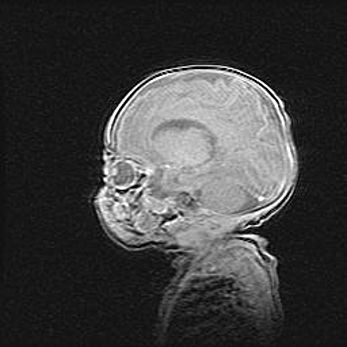

Церебральная ишемия II.

Возраст: 7 дней

Вес: 3350 г

Пол: женский

Окружность головы: 35 см

Срок гестации: 39 недель

Ишемия головного мозга – это состояние, которое развивается в ответ на кислородное голодание вследствие недостаточного мозгового кровообращения. У новорожденных она является следствием дефицита кислорода, что ведет к метаболическим расстройствам различной степени тяжести в тканях головного мозга, в том числе к развитию коагуляционных некрозов и гибели нейронов.